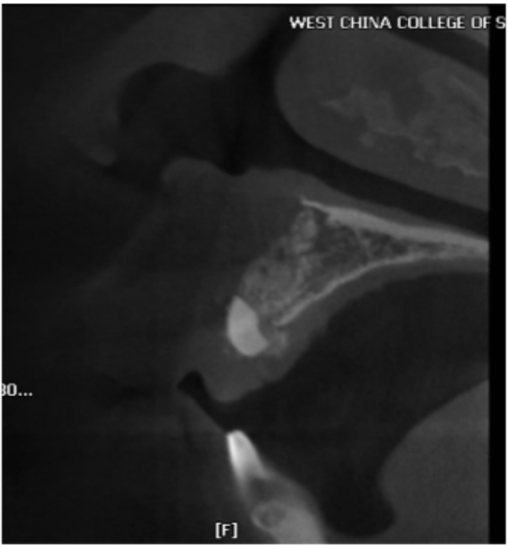

图12 术前CBCT片矢状位显示上颌前牙区的牙槽骨形状细小

图13 术前CBCT片矢状位显示上颌前牙区的牙槽骨形状极度弯曲

图14 术前CBCT片矢状位显示在下颌前牙区的牙槽骨形状非常细,上颌前牙区的牙槽骨高度不足

图15 术前CBCT片矢状位显示下颌前牙区的牙槽骨形状细小而且中份骨质较致密